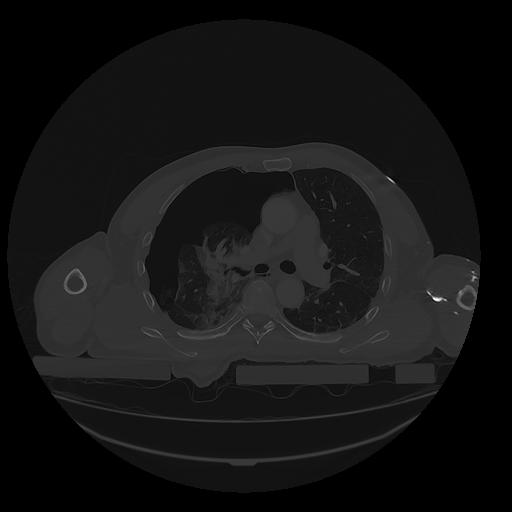

31 PULMON,CE,Vol,1.0,PULMON,,